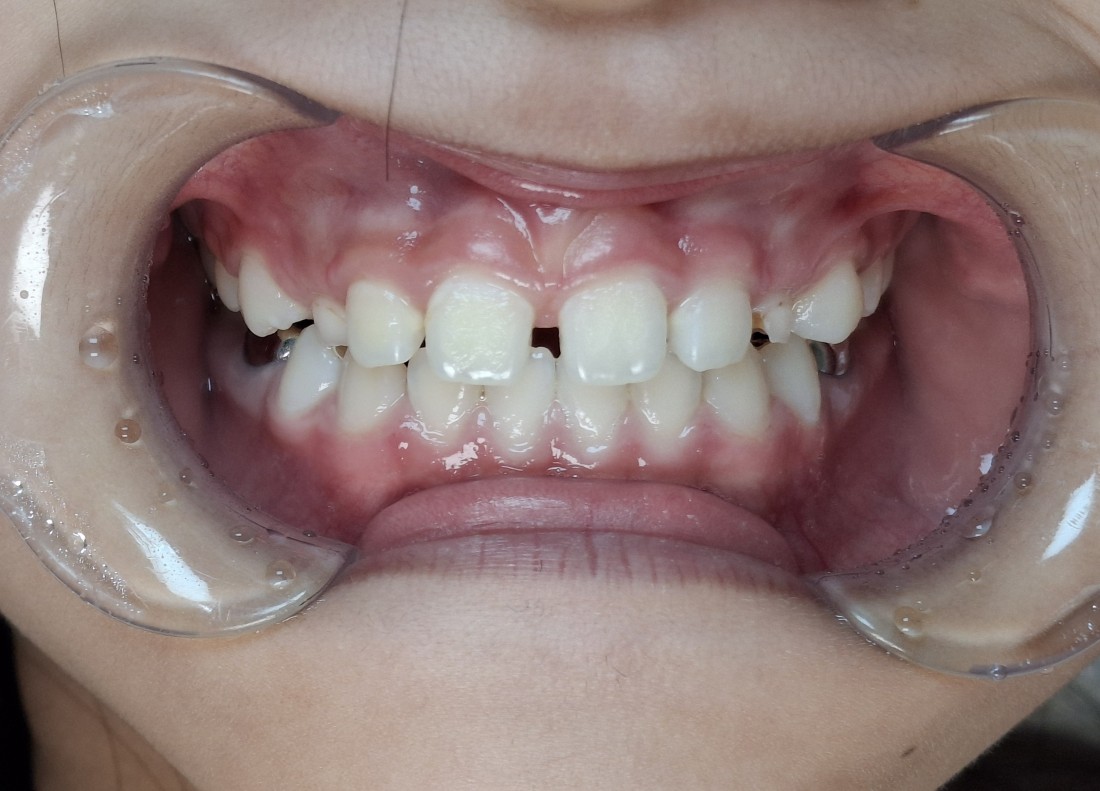

프리올소를 사용하기 최적의 나이는

만5세 ~ 12세 사이의

혼합치열기 (유치에서 영구치로 교환되는 시기)

이기 때문에,

이 골든타임을 잘 지키는 것이

무엇보다도 중요합니다.